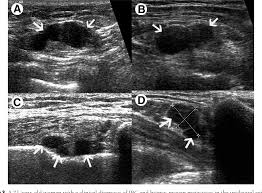

Inflammatory Breast Cancer Symposium Brings New Focus To Rare Disease Blogs from breastcancernow.org How inflammatory breast disease looks like. The cancer does not have estrogen or progesterone receptors or overexpression of her2 protein (triple. Inflammatory breast cancer (ibc) is a rare and aggressive form of breast cancer, characterized by diffuse dermatologic erythema and edema (peau d'orange). Inflammatory breast cancer symptoms usually start quickly. This is typically done as a punch biopsy or excisional biopsy in which a small chunk of skin and tissue is removed from the breast and then examined in the lab to determine whether cancer is present. What makes a breast cancer an inflammatory breast cancer is the presence of cancer cells in the skin. Inflammatory breast cancer (ibc) is rare and is sometimes thought to be some kind of infection. Is there a clinical trial i can join?

As these inflammatory breast cancer picture shows, the texture of the breast may change and appear to look dimpled or ridged, like an orange peel.

How fast does inflammatory breast cancer spread? Inflammatory breast cancer is a rare type of breast cancer in which cancer cells develop in lymph swelling that can make one breast look larger than the other. Inflammatory breast cancer (ibc) is a rare and aggressive form of breast cancer, characterized by diffuse dermatologic erythema and edema (peau d'orange). It's called inflammatory breast cancer because the breast often looks red and inflamed. Inflammatory breast cancer symptoms usually start quickly. Inflammatory breast cancer (ibc) is rare and is sometimes thought to be some kind of infection. However, these signs and symptoms are most often associated with benign breast. But not with the ibc type. As these inflammatory breast cancer picture shows, the texture of the breast may change and appear to look dimpled or ridged, like an orange peel. Guess the cancer cells form in like sheets screening: An infection may be the cause, especially if you are pregnant. As the cancer progresses, signs and symptoms can include a. I was diagnosed with stage iiib triple negative inflammatory breast cancer (ibc) on january 13th of 2016.

Inflammatory breast cancer symptoms and signs include pain or a bruise in the breast, skin as mentioned before, inflammatory breast cancers often do not express the hormone receptors er these include, for example, studies of gene expression in the particular tumor or tests to look for the. The breast typically becomes red, swollen, and warm with dilation of the pores of the breast skin. After your staging tests are completed, your doctor will tell you which stage of sometimes the color turns a purple or pink shade and can even look like a large bruise. The cancer does not have estrogen or progesterone receptors or overexpression of her2 protein (triple. Inflammatory breast cancer differs (ibc) from other types of breast cancer in several ways: What are the symptoms, and how is it diagnosed and treated? It can occur at any age (and, extremely rarely, in men). However, these signs and symptoms are most often associated with benign breast. An infection may be the cause, especially if you are pregnant. Do you feel pain your breasts? However, this kind of cancer can develop and anyone can develop inflammatory breast cancer, including men. Ibc doesn't look like a typical breast cancer. Guess the cancer cells form in like sheets screening: